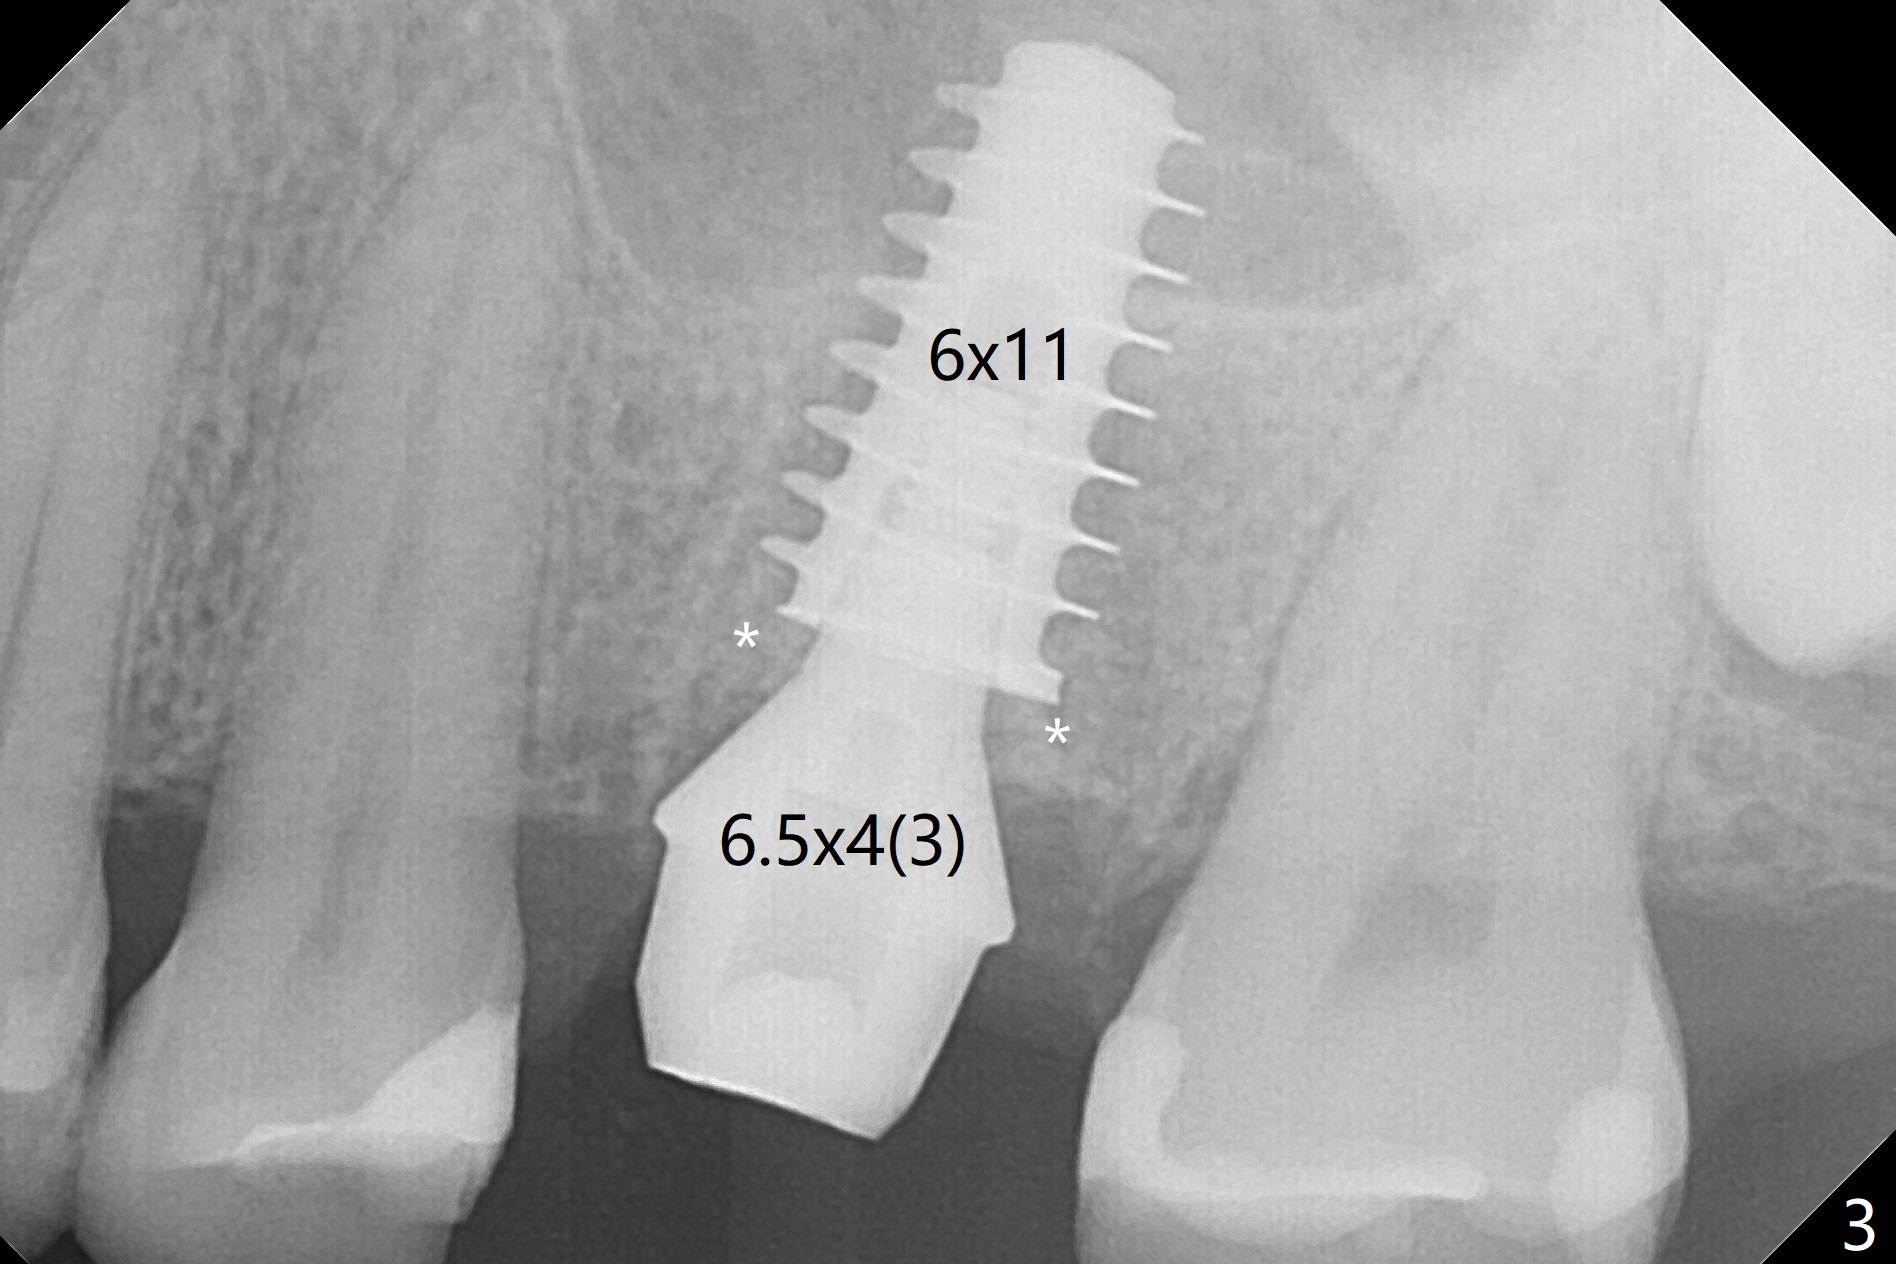

After extraction of the tooth #14 with palatal swelling (Fig.1 *), the septum (S in Fig.2) is found to be thin. Sequential osteotomy quickly deviates to the palatal socket. In spite of using Lindamann bur to remove the bone from the buccal portion of the osteotomy, the apical end of a 5x9 mm dummy implant slides into the palatal socket with the coronal end placed as buccal as possible for restoration (Fig.2 (poor trajectory)). Further use of Lindamann bur for buccal bone removal is not feasible, since the buccoapical portion of the osteotomy starts to be perforated with apparently intact sinus membrane. With insertion of Vanilla graft for sinus lift through the buccoapical portion of the osteotomy mentioned above, a 6x11 mm implant is placed with the same trajectory (Fig.2, <40 Ncm). With placement of a 6.5x4(3) mm abutment (off angle) and of Vanilla graft in the remaining sockets (Fig.2 *), periodontal dressing is applied. When the dressing is dislodged for the 2nd time (12 days postop with healing socket), an angled abutment 5x15 degree, 3 mm cuff, is placed and a provisional is fabricated. There is no sign of sinus infection. The provisional and angled abutment become loose without sinus infection 2 months postop. A 5.5x3 mm healing abutment is placed with light tenderness. If this case turns to be failure, do not stick an immediate implant from potentially infected socket into the sinus in the future. The socket appears to heal 11 months postop (Fig.4). Later a 5x4(3) mm abutment is placed for final restoration. The palatal margin is low. The abutment screw is loose <2 months post cementation, probably due to deep placement and poor trajectory (buccal). It becomes loose again 4 months later. Prior to retightening, a 6 mm profile drill is used. BW shows no bony interference (Fig.5 (opposing tooth occlusal wear; bruxism)), while PA shows the buccal bone, suggesting poor trajectory. The abutment is loose for the 3rd time 17 months post cementation. When the crown/abutment is removed, the hex is worn. After proximal reduction, the crown/abutment feels to be unable to be re-seated. When the crown is sectioned, the abutment itself is incompletely seated (Fig.7,8). The mesial crest appears to interfere with seating (Fig.8). When the 5.2x3 mm dummy abutment is seated, the buccal margin is subgingival, while the palatal one supragingival, suggesting the buccally tilted implant (guided surgery essential). A 4.5x4(4) mm pair abutment seems to be seated completely (Fig.9). The hex of the 5x4(3) mm abutment is worn, but the abutment seems to be able to be seated completely (Fig.11), although not so crisply (easily) as the unworn one clinically. Return to Upper Molar Immediate Implant, Prevent Molar Periimplantitis (Protocols, Table), Armaments Screw Xin Wei, DDS, PhD, MS 1st edition 06/26/2018, last revision 12/20/2020